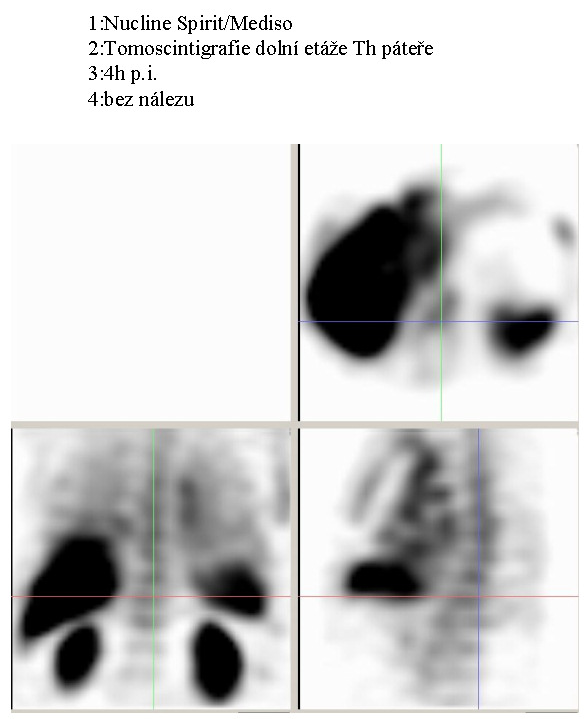

| /Obr. č. 3: SPECT, 4 hod. p.i./ |

/Obr. č. 4: SPECT, 4 hod. p.i./ |